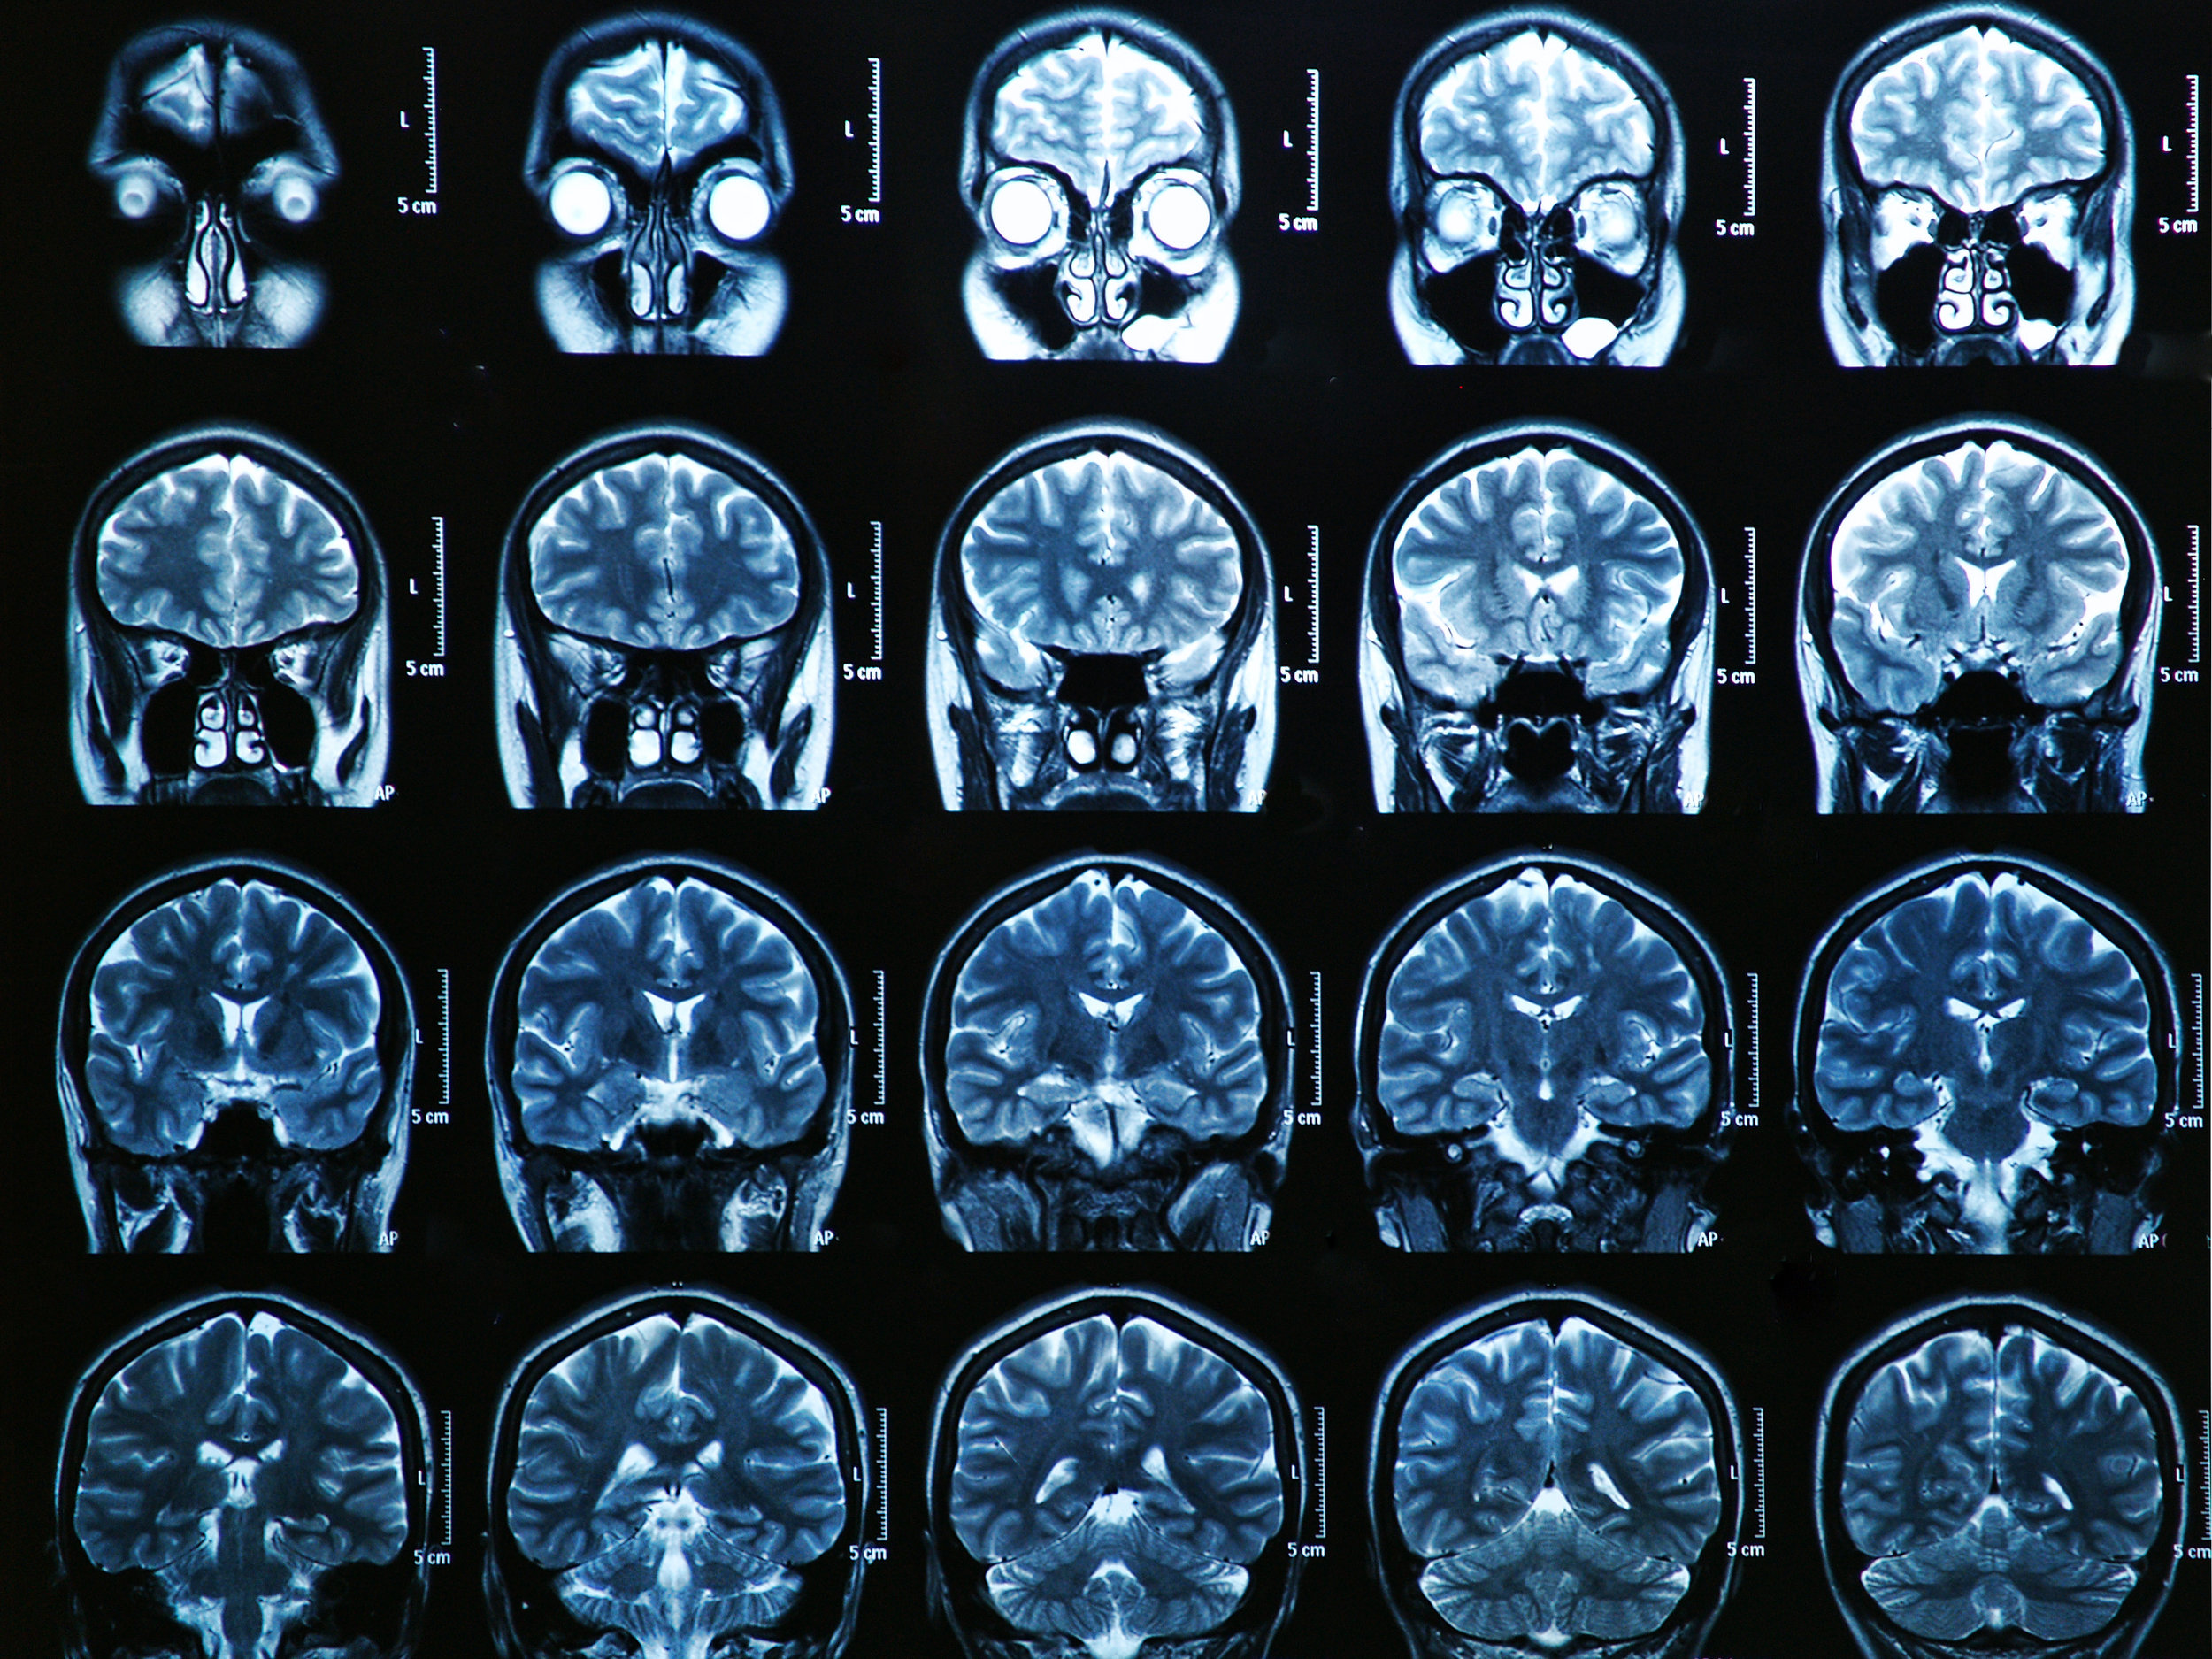

В этом разделе вы найдете примеры снимков МРТ мозга в передней проекции, полезные советы для подготовки к обследованию, а также узнаете, что можно увидеть на таких изображениях.

МРТ головного мозга, что позволяет выявить?

Что показывает МРТ головного мозга

Чем МРТ головного мозга отличается от МРТ сосудов головного мозга